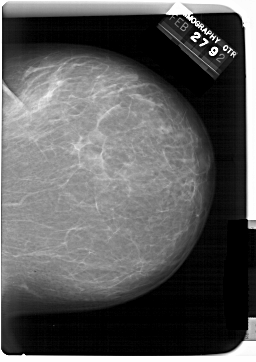

A_1389_1.RIGHT_CC

RIGHT_CC LINES 6871 PIXELS_PER_LINE 4861 BITS_PER_PIXEL 12 RESOLUTION 43.5 NON_OVERLAY